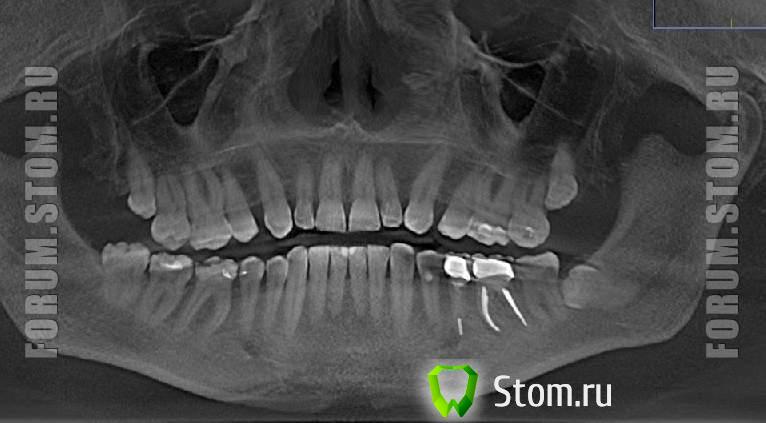

annda Опубликовано 22 ноября, 2011 Поделиться Опубликовано 22 ноября, 2011 ортодонтическое лечение требуется, уже вчера. пациент - вам срочно к ортодонту и не за красотой, а за здоровьем. там вам и ТРГ, КТ назначат и анализ проведут.Судя по отсутствующим 4кам на верхней челюсти,пациент вчера был у ортодонта Просто забыл об этом.А так-то я согласна,проблемы прикуса налицо(е) со всеми вытекающими. Ссылка на комментарий

Oleg-Gru Опубликовано 22 ноября, 2011 Автор Поделиться Опубликовано 22 ноября, 2011 Судя по отсутствующим 4кам на верхней челюсти,пациент вчера был у ортодонта Просто забыл об этом.А так-то я согласна,проблемы прикуса налицо(е) со всеми вытекающими. Так то было не вчера, а лет 30 назад. Какие проблемы с прикусом вы видите ? Ссылка на комментарий

annda Опубликовано 22 ноября, 2011 Поделиться Опубликовано 22 ноября, 2011 Я лучше к Снежанне присоединюсь,в инете не буду развёрнутые консультации и анализы проводить.Многие знания инет-пациентов-многия печали докторов,потом в реале их встречающих.Соберётесь лечиться,ищите доктора,слушайте его,можете не одного послушать,выбирайте,кто вам больше по сердцу придётся и лечитесь.Это ИМХО.Проблемы есть и они вытекают из удаления 4к на верхней челюсти в том числе.Они,возможно ,были бы и без этого,но в гораздо меньшем масштабе.ИМХО. Ссылка на комментарий